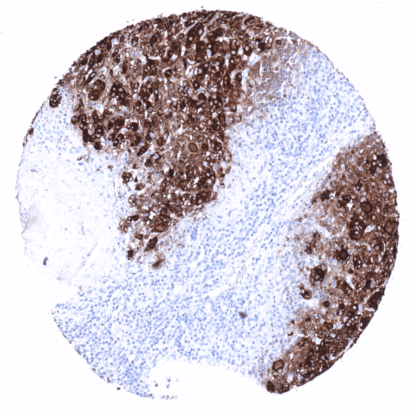

Recombinant Rabbit monoclonal / IgG 1:100 – 1:200 Research Use Only Cytoplasmic Human MSVA-189R AITD3, hTG, TDH3, Tg, Tgn Thyroid: A strong staining is seen in follicular cells and the colloid. The stroma is typically also stained due to a  contamination artifact. Colon: All cells must not show any staining. Thyroglobulin is a 660 kDa glycoprotein encoded by the TG gene located at human chromosome 8q24.22. The glycoprotein is predominantly expressed by follicular cells of the thyroid gland and assembles into homodimers which are secreted into the follicular lumen. Thyroglobulin is the substrate for the synthesis of thyroxine and triiodothyronine, two major hormones of the thyroid gland, and serves as a storage protein for the inactive forms of these hormones in the follicular colloid. Polymorphisms of the TG gene have been linked to susceptibility of autoimmune thyroid diseases including Hashimoto thyroiditis.[1] Thyroglobulin is a 660 kDa glycoprotein encoded by the TG gene located at human chromosome 8q24.22. The glycoprotein is predominantly expressed by follicular cells of the thyroid gland and assembles into homodimers which are secreted into the follicular lumen. Thyroglobulin is the substrate for the synthesis of thyroxine and triiodothyronine, two major hormones of the thyroid gland, and serves as a storage protein for the inactive forms of these hormones in the follicular colloid. Polymorphisms of the TG gene have been linked to susceptibility of autoimmune thyroid diseases including Hashimoto thyroiditis. [1] [1] Steurer et al.: “Immunohistochemically detectable thyroglobulin expression in extrathyroidal cancer is 100% specific for thyroidal tumor origin” . Published in Annals of Diagnostic Pathology, Volume 54, October 2021, 151793 In normal tissues, thyroglobulin immunostaining is exclusively seen in thyroid tissue. In the thyroid, immunostaining often not only involves follicular epithelial cells but also stroma and other cell types. This is due to the abundance of thyreoglobulin in the thyroid. Thyroglobulin makes up for about half of the protein mass of the thyroid. In case of immunostaining, some thyroglobulin spill-over occurs resulting in a staining of follicle-adjacent tissues. These findings are largely comparable to the data described in the Human Protein Atlas (Tissue expression Thyroglobulin) . Suggested positive tissue control : Thyroid: A strong staining is seen in follicular cells and the colloid. The stroma is typically also stained due to a  contamination artifact. Suggested negative tissue control: Colon: All cells must not show any staining. Thyroid gland – Very intense thyroglobulin immunostaining in follicular cells. Due to the large quantity of thyroglobulin in a normal thyroid (50% of the p... Thyroglobulin expression is only found in tumors derived from the thyroid and in metastases from extrathyroidal tumors to the thyroid. In the case of metastases to the thyroid, tissue contamination by colloid from potentially destructed adjacent follicles is likely to cause unexpected positivity in a fraction of cases. For the same reason thyroglobulin immunostaining can also be seen in medullary (or anaplastic) carcinomas of the thyroid, which do not express thyroglobulin. Detailed data on Thyroglobulin staining by MSVA-189R obtained from an analysis of >9000 tumors from 109 different tumor types and subtypes have recently been published Steurer et al.: “Immunohistochemically detectable thyroglobulin expression in extrathyroidal cancer is 100% specific for thyroidal tumor origin” . – Detailed data below “Compatibility of Antibodies” The TCGA findings on Thyroglobulin RNA expression in different tumor categories have been summarized in the Human Protein Atlas. Follicular thyroid cancer... Thyroglobulin (MSVA-189R) publication summary Paper used for data compilation: Steurer et al.: “Immunohistochemically detectable thyroglobulin expression in extrathyroidal cancer is 100% specific for thyroidal tumor origin” . Published in Annals of Diagnostic Pathology, Volume 54, October 2021, 151793 In this study, a total of 9974 tumors were analyzed from 109 different tumor categories by using the following protocol: Heat-induced antigen retrieval for 5 minutes in an autoclave at 121°C in pH 6 Target Retrieveal Solution buffer. MSVA-189R at a dilution of 1:135 at 37°C for 60 minutes. Visualization of bound antibody by the EnVision Kit (Dako, Agilent). This protocol was also used for all stainings depicted in our tumor and normal tissue galleries. The distribution of positive staining results is shown in an “organ-systematic” and in a “ranking order” figure below (images based on a compilation of data from Steurer et al. ). A positive thyroglobulin immunostaining was only seen in tum... IHC users have different preferences on how the stains should look like. Some prefer high staining intensity of the target stain and even accept some background. Others favor absolute specificity and lighter target stains. Factors that invariably lead to more intense staining include higher concentration of the antibody and visualization tools, longer incubation time, higher temperature during incubation, higher temperature and longer duration of the heat induced epitope retrieval (slide pretreatment). The impact of the pH during slide pretreatment has variable effects and depends on the antibody and the target protein. All images and data shown here and in our image galleries are obtained by the manual protocol described below. Other protocols resulting in equivalent staining are described as well. Manual protocol Freshly cut TMA sections were deparaffinized and exposed to heat-induced antigen retrieval for 5 minutes in an autoclave at 121°C in pH 6 Target Retrieval Solution buffer. A... No data available at the moment. Specificity of MSVA-189R is documented by strong positive staining thyroid follicular cells in combination with complete absence of any thyroglobulin immunostaining in any other normal tissues. Normal tissue gallery